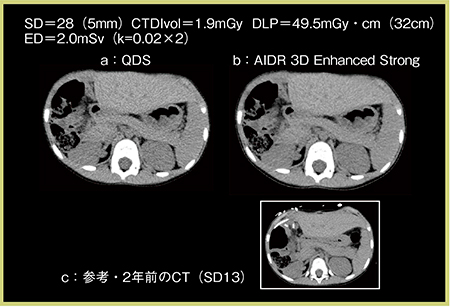

2.単純CT

単純CTはコントラストがつきにくいため,SD28(5mm)で撮影している。症例2は,6歳,女児,生体肝移植後フォローだが,QDS,AIDR 3D Enhanced Strongで鮮明な画像が描出されている(図3)。図3 cは,2年前にSD13で撮影された肝移植後のCT画像だが,SD28+AIDR 3D Enhanced Strong(図3 b)では,ほぼ遜色ない画質が得られている。コントラストが得にくい上腹部の単純CTにおいても,SD28(5mm)+AIDR 3D Enhancedを選択することで,低線量での撮影が可能である。

図3 症例2:小児体幹部の単純CT

a:QDS b:AIDR 3D Enhanced Strong c:2年前のCT(SD13)